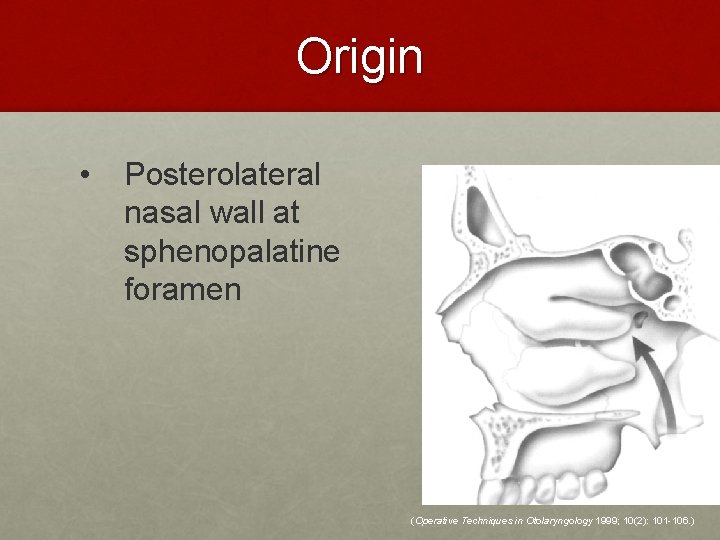

Origin • Posterolateral nasal wall at sphenopalatine foramen (Operative Techniques in Otolaryngology 1999; 10(2): 101 -106. )